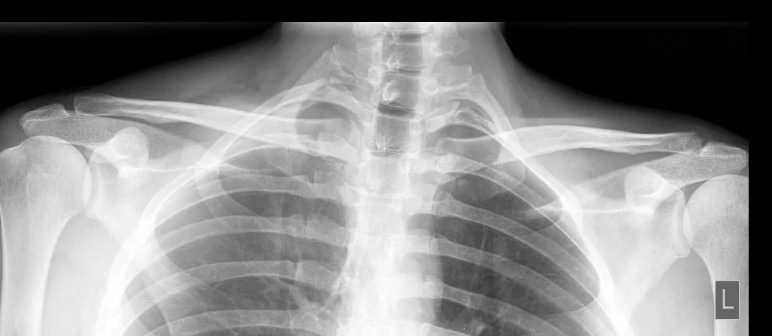

На рентгенограмме парных суставов есть возможность сравнить их состояние. На снимке будут видны:

• Перелом одной или обеих ключиц;

• Расширение суставной щели;

• Отстояние края ключицы от акромиона вследствие вывиха;

• Остеофиты и другие дегенеративные изменения;

• Отек мягких тканей.